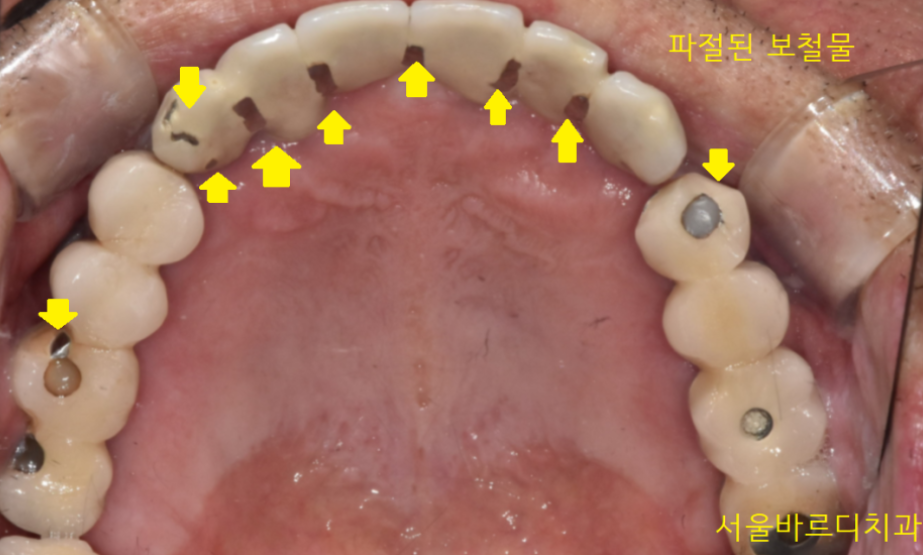

이런식으로 말이죠!

그래서 턱 근육 발달이 잘 되어있는 남성분들

씹는 힘이 강하신 분들은

씹는 면 역시 metal로 만듭니다.

쇠는 깨지지 않으니까요.

사진을 볼까요~?

안예쁘죠~?

특히 아래 어금니의 경우

웃을때, 말할 때

쇠 색깔이 너무 잘보입니다!!

경우에따라 임플란트 크라운 씹는면을

쇠로 다 덮어버리기도 합니다.